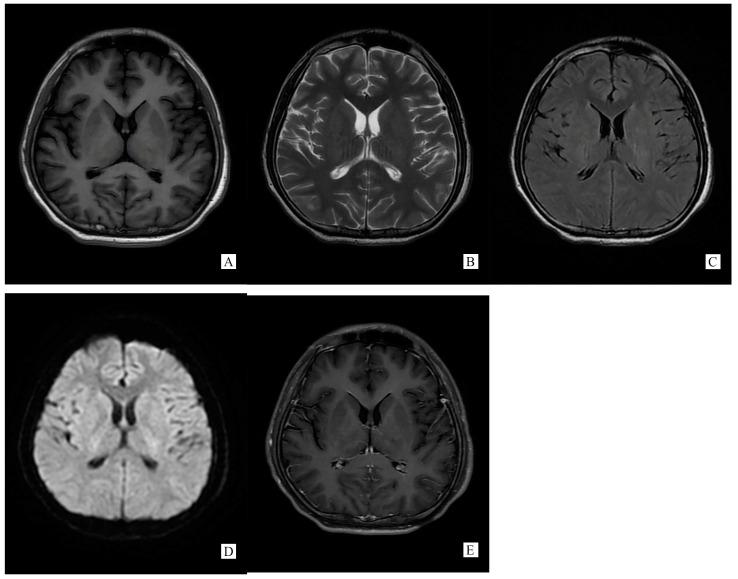

we reported a case developing irregularly high fever, both temporal pain, low limbs fatigue with frequent urination admitted to our neurology department. CSF test showed GFAP-IgG positive, elevated WBC counts and protein, with low glucose and chlorine, while MRI showed a reversible lesion on SCC, leading us to diagnose autoimmune GFAP autocytopathy accompanied with RESLES. The boy had significantly improved after anti-virus and steroids therapy.

我们报告了一例因不规则高热、双侧颞部疼痛、下肢乏力伴尿频入住我院神经内科的病例。脑脊液检查显示GFAP-IgG阳性,白细胞计数及蛋白升高,葡萄糖和氯化物降低,而磁共振成像显示胼胝体压部有可逆性病变,从而诊断为自身免疫性GFAP星形细胞病伴RESLES。该男孩在抗病毒及类固醇治疗后有明显改善。